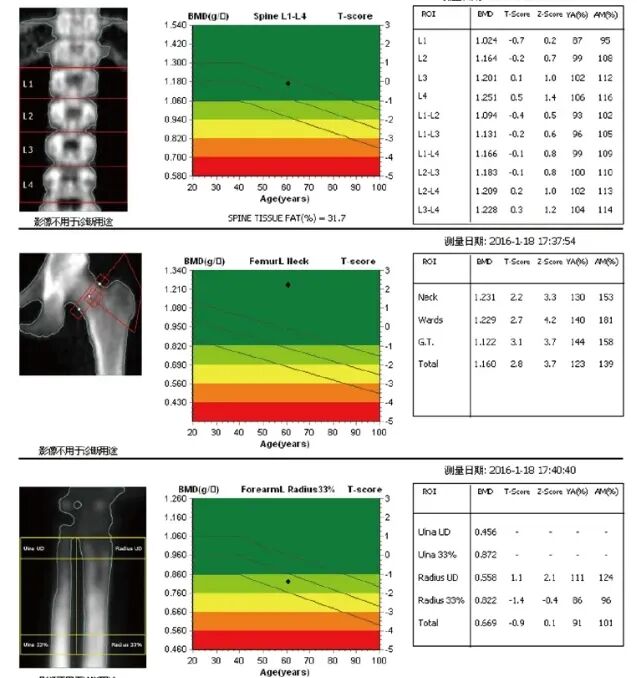

(检测报告)